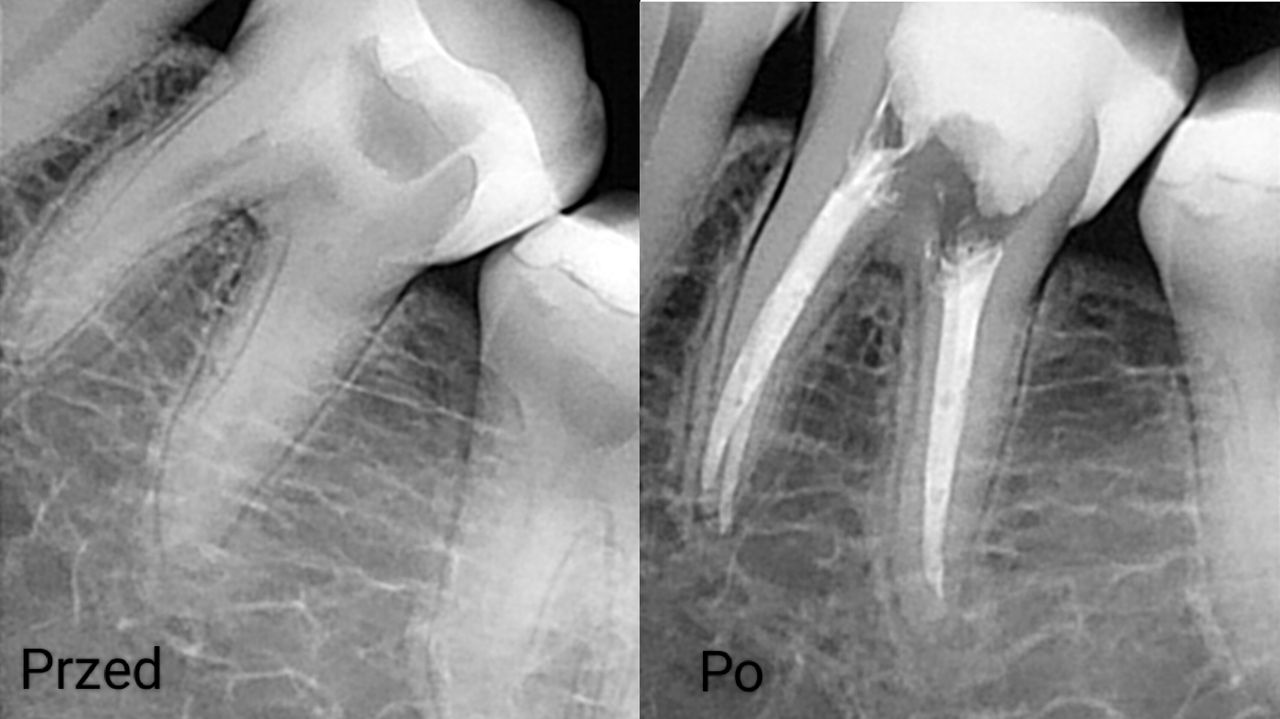

Na co dzień zajmuję się głównie stomatologią zachowawczą oraz leczeniem endodontycznym z wykorzystaniem mikroskopu. Wykonuję leczenie próchnicy i jej powikłań zarówno u dorosłych, jak i u dzieci. Zajmuję się również zabiegami higienizacji, wybielaniem zębów, leczeniem niepróchnicowych zmian szkliwa metodą ICON

Zdjęcia i filmy

Leczenie endodontyczne